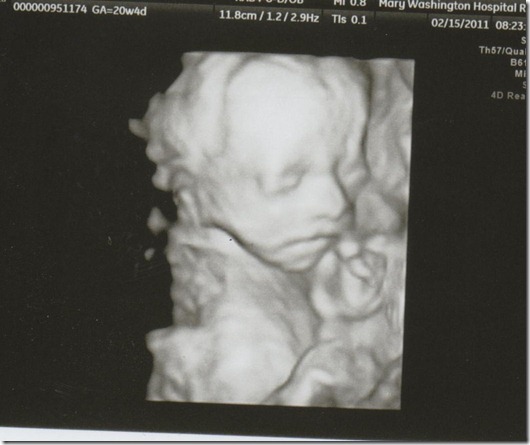

Meet Maisy!

And after seeing her sweetness at the sonogram today I am more than ready for her to get here too!!  I got to watch her in 3d/4d for a while and she was just sucking her thumb, being so cute.  She even gave us the #1 sign!

The appointment went good, she’s measuring right on target!  She weighs 14 ounces and her heartrate was 150bpm.  They did a blood flow study on her and the Doctor spent some time looking for all of the major artery’s that run through the brain.  He was able to locate all except for one, but didn’t seem concerned because he said it could have just been her position.  When I go back in 4 weeks they will look again.  He was able to review Ryder’s MRI report and confirmed that the stroke did happen in-utero, so based on that he wants me to start taking a baby aspirin a day.  Aspirin crosses the placenta and will thin her blood.  The chances of something similar happening to her are very slim, but I guess he just feels like it’s worth taking the extra precautions.  Fine with me, I’ll do anything I can to keep my sweet little Maisy safe!